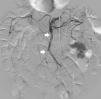

Initially, we opted for a conservative approach with anticoagulant therapy (heparin). The progression of the patient's condition became torpid, with more pain and guarding in the right hemiabdomen. The leukocytosis continued, associated with neutrophilia and mild metabolic acidosis. Given the worsening symptoms, we decided to perform CT angiography, which showed evidence of a small repletion defect at the origin of the ileocolic artery, with distal opacification related with a partially occlusive thrombus. The ileal loops located in the iliac fossa and right flank presented intestinal suffering (Fig. 1). Given the hemodynamic stability, we decided to perform a radiological approach using arteriography of the SMA, where a dissection flap was observed within the first few centimeters, causing obstruction of all the ileal branches, with no evidence of stenosis at the origin (Fig. 2).

Endovascular treatment was not considered indicated by the interventional radiology department because of the risk for aggravating the vascular obstruction.